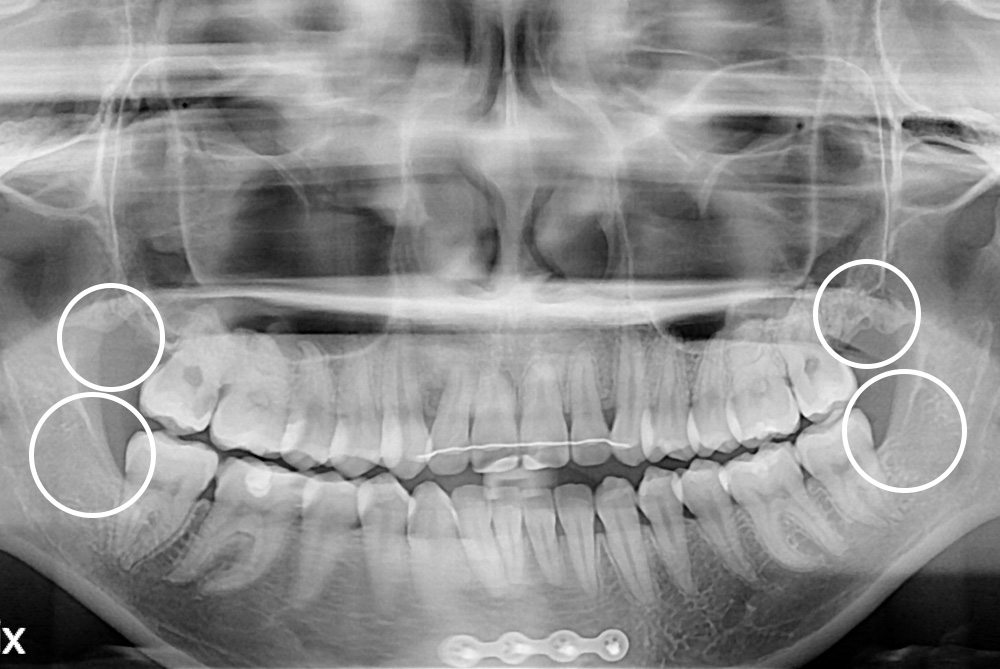

[사랑니] 매복 사랑니 발치

치료전 : 2021-04-12

세종치과는 구강악안면외과학 박사이신 원장님이 발치하는 치과입니다.